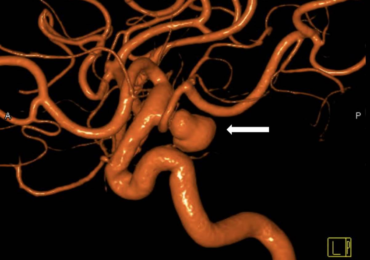

Figure 7. Trap and bypass of a ruptured dissecting Posterior Inferior Cerebellar Artery (PICA) aneurysm. 1. Lateral view of the dissecting aneurysm (arrow). 2. Demonstration of the planned clip locations (grey bars) to trap the aneurysm and the cut (red bar) with the proposed reconnection (bypass) to reconnect the artery to the blood flow and prevent a stroke. 3. After the trapping (white clips) and bypass there is preserved blood vessel flow and the aneurysm is trapped between the clips and is no longer at risk of rupture.